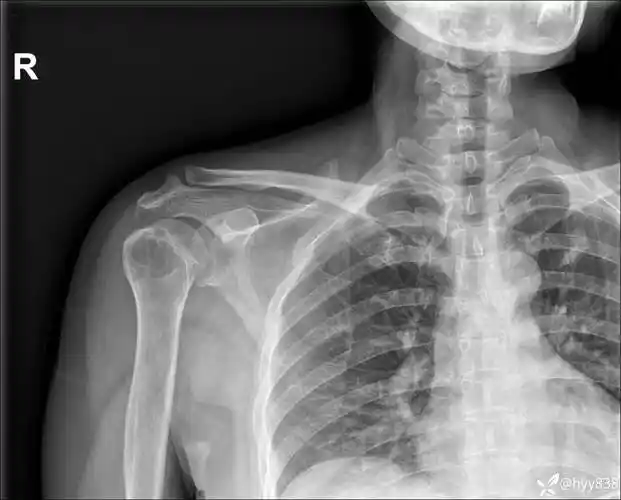

肩关节正位-x线图

中年女性,发现右肩关节占位2天.有特征,有细节---(有结果)

右肩关节间隙,肩峰下滑囊,喙突下滑囊少量积液.